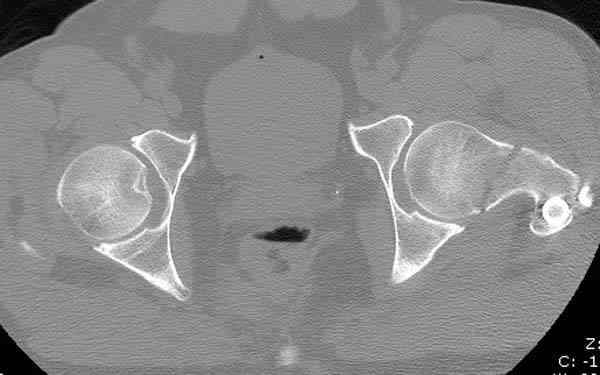

Здесь представлены снимки больного 65 лет, поступившего с диагнозом перелом

бедра после автоаварии.

В первый же день произведено антеградное штифтованием DePuy Trochanteric Nail.

На второй день (7) обнаружен пропущенный перелом,

сделаны Компьютерная Томограмма

и проведены шурурпы через и спереди штифта без удаления.

Послеоперационные снимки